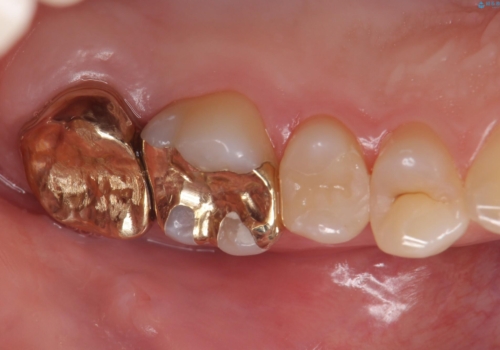

奥歯の虫歯の治療

- 奥歯が虫歯になっていたため治療しました。

奥は高さを取るのが難しかったため薄く作れる金属(ゴールド)で治療しています。

- 合計 26.4万円(内訳:右上7 PGAクラウン 11万円(旧料金)、右上6PGAインレー 7.7万円(旧料金)、右上5 emaxインレー 7.7万円)費用は治療当時の料金となります